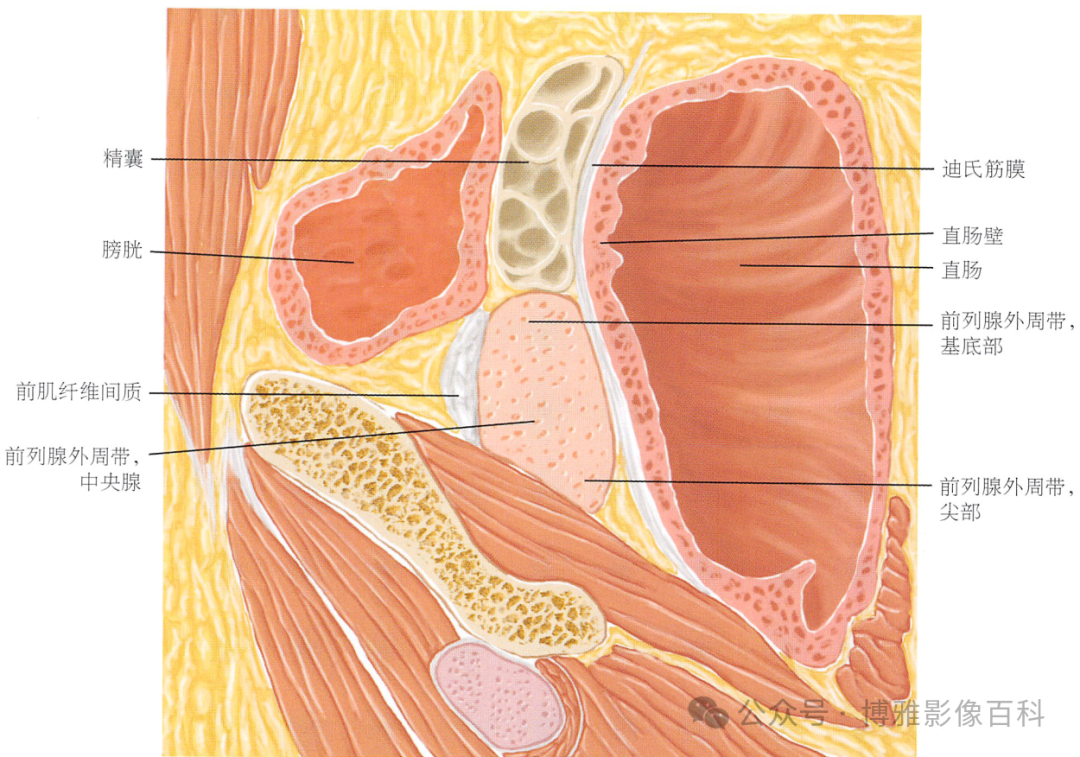

解剖学

前列腺分区解剖学

MR 解剖学

前列腺良性增生患者的轴向T2 图像,其他方面正常。外周带是一薄层均匀的高信号,边界清晰连续性的低信号包膜。移行带通常表现为不均匀中等信号,病灶被边界清楚的BPH良性前列腺增生结节所取代。精囊具有均匀T2高信号。未见淋巴结肿大。